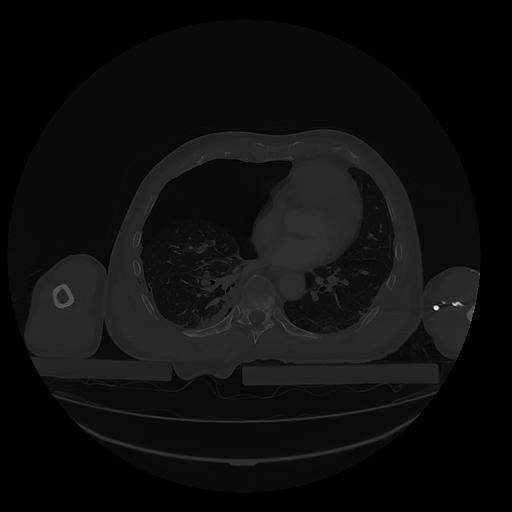

31 PULMON,CE,Vol,1.0,PULMON,,